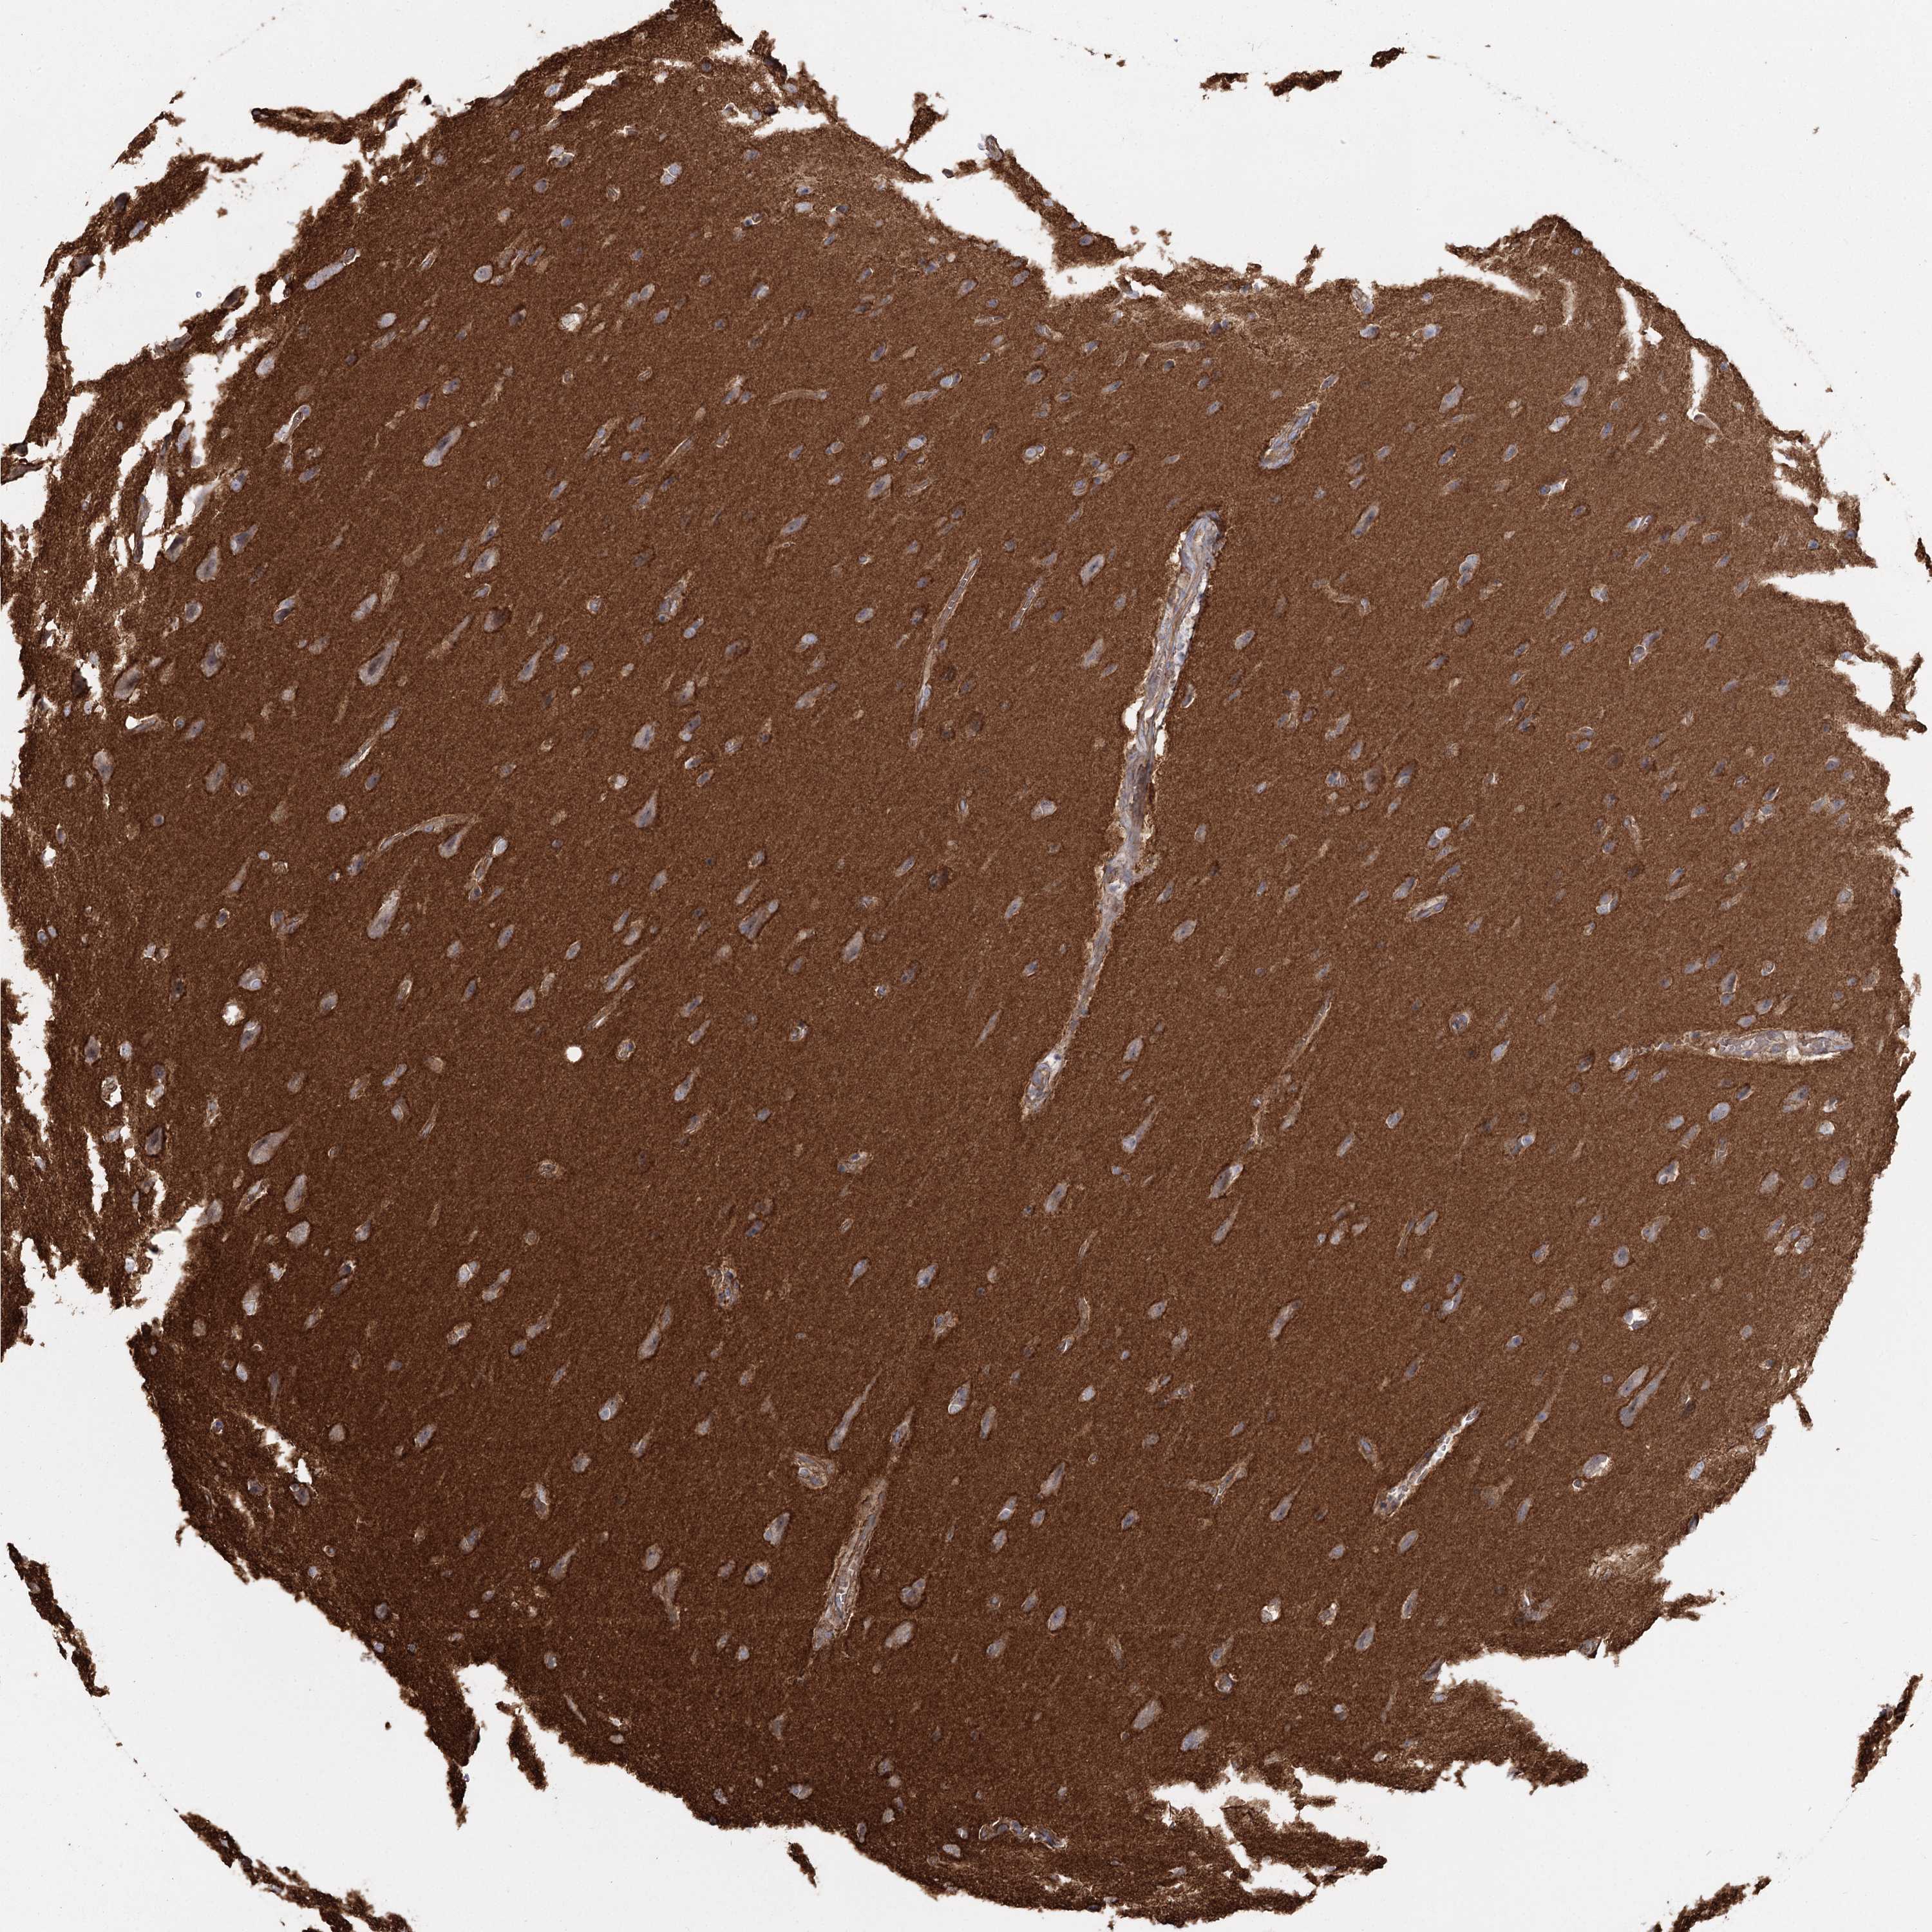

GLIOMA - Protein expressioni

A mouse-over function shows sample information and annotation data. Click on an image to view it in a full screen mode. Samples can be filtered based on level of antibody staining by selecting one or several of the following categories: high, medium, low and not detected. The assay and annotation is described here.

Note that samples used for immunohistochemistry by the Human Protein Atlas do not correspond to samples in the TCGA dataset.

Antibody stainingi

Antibody staining in the annotated cell types in the current human tissue is reported as not detected, low, medium, or high, based on conventional immunohistochemistry profiling in selected tissues. This score is based on the combination of the staining intensity and fraction of stained cells.

Each image is clickable and will lead to virtual microscopy that enables deeper exploration of all samples and also displays staining intensity scores, fraction scores and subcellular localization as well as patient and tissue information for each sample.

Antibody HPA036194

Staining

High

Medium

Low

Not detected

Intensity

Strong

Moderate

Weak

Negative

Quantity

>75%

75%-25%

<25%

None

Location

Nuclear

Cytoplasmic/membranous

Cytoplasmic/membranous,nuclear

Glioma, malignant, Low grade

Glioma, malignant, High grade

Glioblastoma, NOS